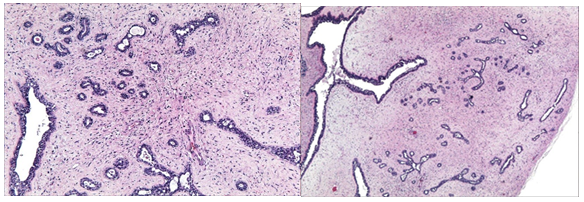

The excised specimen on macroscopic examination showed a firm mass measuring 2.5x1.5x0.7cms. Cut surface was grey- white. There was no cyst. Areas of haemorrhage and necrosis were absent. Microscopy showed epithelial and stromal proliferation. Glandular elements were benign and ranged from small rounded gland like structures to branched ducts and displayed myoepithelial cells. There was no evidence of atypia. Fibrocollagenous stroma showed mild increase in cellularity in the periglandular areas (Figure 1). Immunohistochemical studies were done and the glandular cells showed strong positivity immunoreactivity for ER and PR (Figure 2A) (Figure 2B). These histopathologic findings were of vulvar fibroadenoma.

Figure 1A & 1B (H&E x10) Microscopic picture showing glandular and stromal components of fibroadenoma.